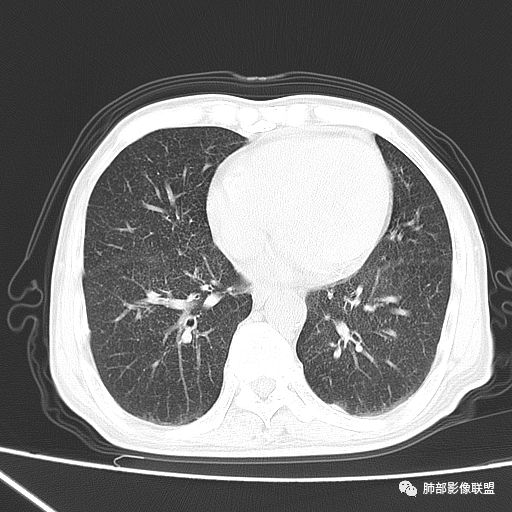

2019-10-20复查CT如下:

两肺弥漫性粟粒样结节伴左上肺小结节,呈三均匀分布,有结核的临床表现,支持血性播散性肺结核。

大小、分布均匀,边缘清楚

细小结节,弥漫,撒米粒样——血道来源

部分可见分支状

南边:

边缘稍平直

毛刺细弱

还是支持结核

血道来源的病灶,均匀、细微,而且部分有分支状,都符合粟粒型肺结核

糖尿病病史也支持

鉴别转移瘤,太细微、太均匀,而且8~11月,会增大

癌,一般淋巴道分布,不是血道

急性血行播散型肺结核  两肺广泛分布粟粒大小的结节状密度增高影,具有大小均匀、分布均匀、密度均匀的典型“三均匀”特征,注意急性血播病灶非常小,一般粟粒影直径1~2mm。

病灶密集者出现肺外围血管影不清或减少。

发热初期肺部可缺乏典型影像学改变,1到2周后出现的广泛粟粒结节对诊断具有高度提示作用!